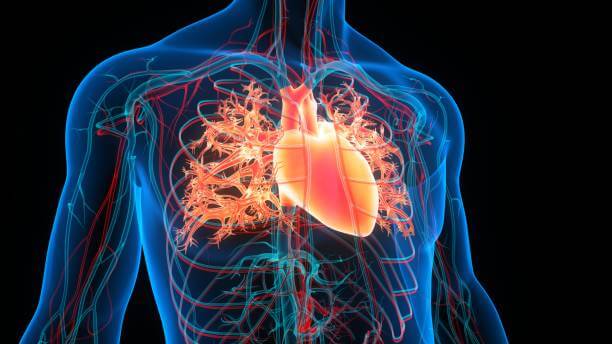

협심증(心絞痛), 일반적으로 '협심증' 또는 '협심증'으로 불리는 이 질환은 심장의 혈액 공급이 감소되어 발생하는 가슴 통증을 말합니다. 협심증은 주로 심장의 혈관인 관상동맥이 좁아지거나 막히면서 발생하는 상황에서 나타납니다. 이는 주로 협심증의 가장 일반적인 원인인 관상동맥 질환으로 인해 일어납니다.

심장은 산소와 영양분을 공급받기 위해 관상동맥을 통해 혈액을 받아옵니다. 그러나 협심증이 발생하면 관상동맥의 혈액 흐름이 부족하게 되므로 심장에 필요한 혈액 공급이 충분하지 않게 됩니다. 이는 심장 근육을 구성하는 세포들이 영양분과 산소를 충분히 받지 못하게 되어 가슴 통증을 일으킵니다.